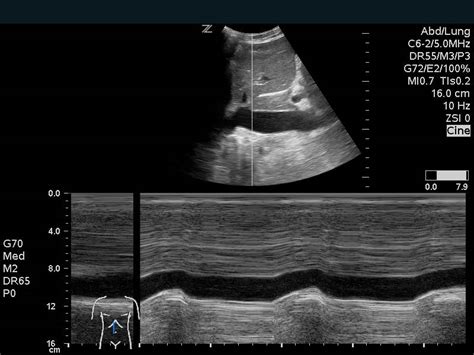

Echocardiography (Echo): Your Heart’s Ultrasound Buddy

This is probably one of the most widely used and accessible cardiac imaging techniques. Think of it like the ultrasound your parents might have had when expecting a baby, but this one’s focused on your heart. Echocardiography , or ‘echo’ for short, uses high-frequency sound waves to create moving pictures of your heart. A technician will place a transducer (a small probe) on your chest, and these sound waves bounce off your heart structures, creating echoes that are then converted into images. It’s completely non-invasive and painless . Doctors use echo to assess the size and shape of your heart, the thickness of its walls, how well the chambers are pumping, and the function of your heart valves. It’s fantastic for detecting valve problems, congenital heart defects, and issues with the heart muscle itself, like hypertrophic cardiomyopathy. There’s also something called a ‘stress echo,’ where they do an echo before and after you exercise (or are given medication to simulate exercise) to see how your heart performs under stress – super useful for spotting coronary artery disease.